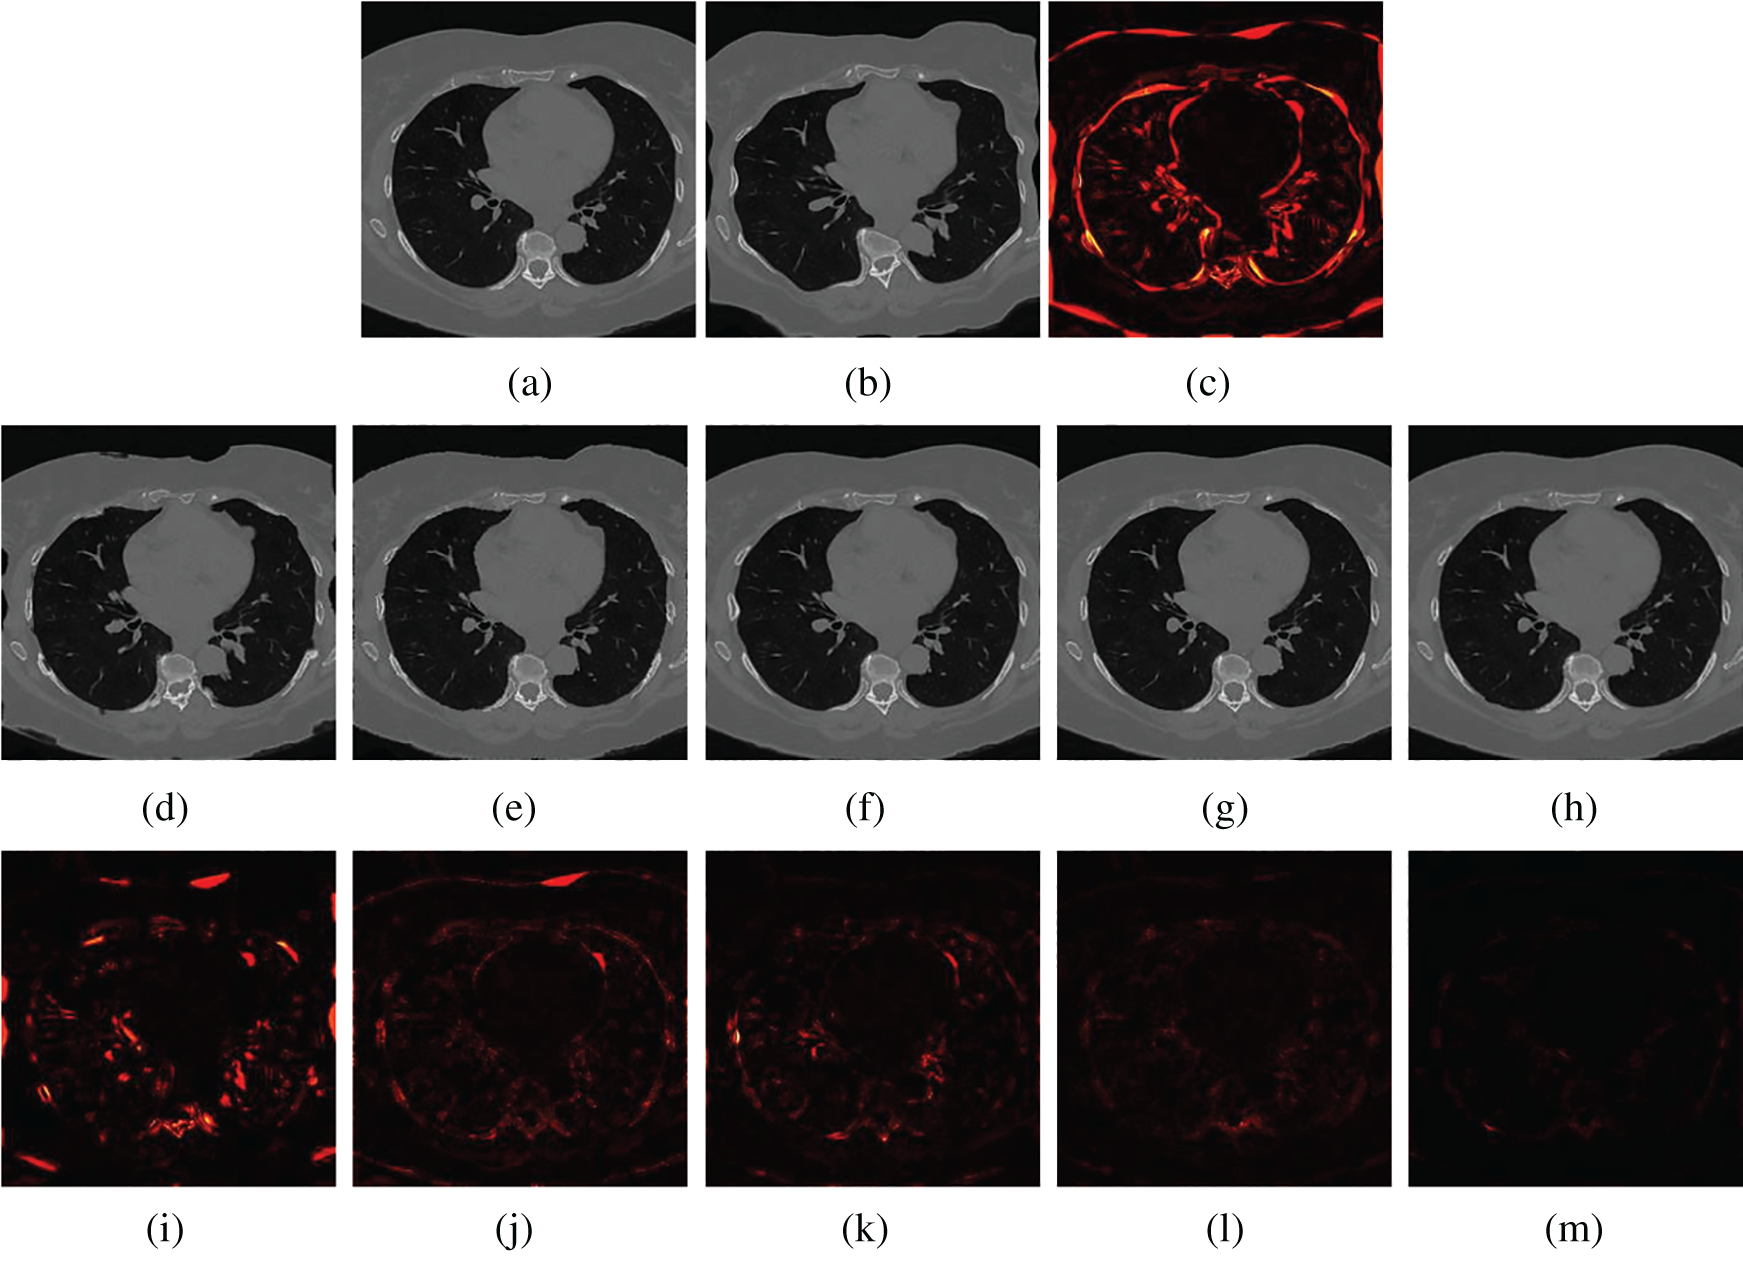

Figs. 5 and 6 show two examples of registration results with different methods (Demons, SIFT Flow, Elastix, VoxelMorph, and the proposed Siamese Flow) from the test BrainWeb and EMPIRE10 datasets. Fig. 5a is the fixed T1 image; Fig. 5b is the moving T1 image; Fig. 5c is the heatmap between the fixed and moving images; Figs. 5d–5h are the registered images obtained by Demons, SIFT Flow, Elastix, VoxelMorph and Siamese Flow, respectively; and Figs. 5i–5m are the heatmaps between the fixed and registered images. The heatmap shows the absolute difference between the fixed and registered images. Figs. 5 and 6 show that the heatmaps of the five methods are consistent with their RMSD and DICE results, and the proposed Siamese Flow achieves the most accurate registration results.

Figure 5: Visualization of registration accuracy results using a heatmap for a randomly selected BrainWeb T1 image and its deformable image (λ = 150). (a) Fixed T1 (b) Moving T1 (c) Heatmap of the fixed and moving T1 (d) Demons (e) SIFT Flow (f) Elastix (g) VoxelMorph (h) Siamese Flow (i) Heatmap of Demons (j) Heatmap of SIFT Flow (k) Heatmap of Elastix (I) Heatmap of VoxelMorph (m) Heatmap of Siamese Flow

Figure 6: Visualization of registration accuracy results using a heatmap for a randomly selected EMPIRE10 image and its deformable image (λ = 150). (a) Fixed image (b) Moving image (c) Heatmap between the fixed and moving image (d) Demons (e) SIFT Flow (f) Elastix (g) VoxelMorph (h) Siamese Flow (i) Heatmap of Demons (j) Heatmap of SIFT Flow (k) Heatmap of Elastix (I) Heatmap of VoxelMorph (m) Heatmap of Siamese Flow